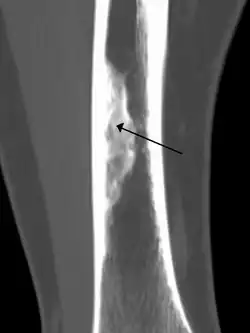

An ossified non-ossifying fibroma on CT

Diagnosis is by X-ray or MRI, usually when investigating a person for something else.[2] Medical imaging typically shows a well defined radiolucent lesion, with a distinct multilocular appearance, sometimes looking like bubbles.[2] It is usually around 1–2 cm in size, but be as large as 7 cm.[3] They consist of foci consist of collagen rich connective tissue, fibroblasts, histiocytes and osteoclasts.[2] Usually no treatment is required.[1] Surgical curettage and bone grafting may be required if it is large.[3]

It is usually diagnosed by x-ray or MRI, when investigating another problem.[1] The tumor presents as a well defined radiolucent lesion, with a distinct multilocular appearance, sometimes looking like a "soap bubble".[5] If small and no symptoms, then biopsy is not needed.[1]